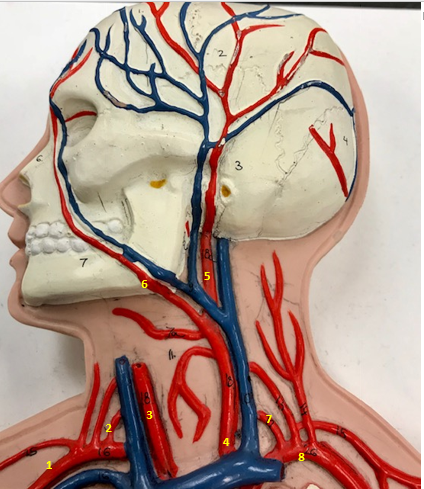

Right subclavian artery

Name #1

Supplies blood to right arm and shoulder

Function of right subclavian artery (1)

Right vertebral artery

Name #2

Supplies blood to brain and spinal cord

Function of right vertebral artery (2)

Right common carotid artery

Name #3

Supplies blood to right neck and head

Function of right common carotid artery (3)

Left common carotid artery

Name #4

Supplies blood to left neck and head

Function of left common carotid artery (4)

Left external carotid artery

Name #5

Supplies blood to face neck and skull

Function left external carotid artery (5)

Left facial artery

Name #6

Supplies blood to face and neck

Function of left facial artery (6)

Left vertebral artery

Name #7

Supplies blood to brain and spinal cord

Function of left vertebral artery (7)

Left subclavian artery

Name #8

Supplies blood to left arm and shoulder

Function of left subclavian artery (8)